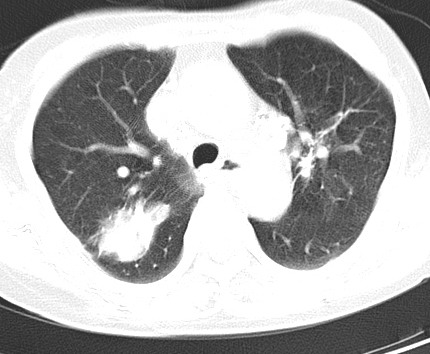

以下是引用hhcckk在2007-3-2 14:51:00的发言:[br]考虑结核球可能性大,依据[br]1病灶在下叶背段,结核的好发部位[br]2病灶内有大量的钙化,纵隔内有大量的淋巴结钙化[br]3重要的是半年前与现在相比无变化,假如是肿瘤的话不会这么‘善良’[br]4病灶周围卫星灶不明显,病灶有毛刺,胸膜凹陷,肿瘤不能完全排除,有条件的话最好做个活检

以下是引用liuyue在2007-3-2 17:15:00的发言:[br]1位置:右上叶后段[br]2性质:大分叶、粗长毛刺、条状斑片状钙化、纵隔多发淋巴结钙化,无强化,故考虑:肺结核灶(陈旧)